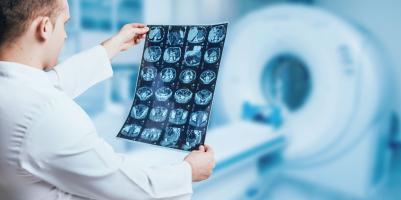

GLIOBLASTOME : Il affecte bien plus que le cerveau

Actualité publiée le 10/04/2026GLIOBLASTOME : Comment la tumeur se nourrit de sucre

GLIOBLASTOME : Des changements alimentaires pourraient ralentir le cancer

GLIOBLASTOME : Prévenir l’évasion de cette tumeur cérébrale mortelle

GLIOBLASTOME : Une régression spectaculaire avec une nouvelle thérapie « CAR-TEAM »

GLIOBLASTOME : Ettouffer les cellules tumorales

GLIOBLASTOME : Les promesses d’un médicament de l’Alzheimer

GLIOBLASTOME : Convertir les cellules de gliome en neurones sains, c'est possible

GLIOBLASTOME : Une pompe ionique pour délivrer ciblé la chimio au cerveau

GLIOBLASTOME : Ensemencement et traitement à partir d’un site distant ?